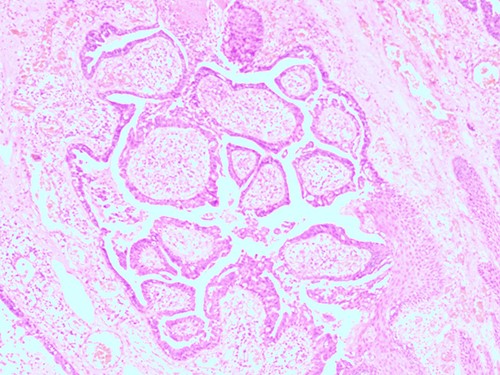

The histopathological examination found cystic invaginations of the infundibular epithelium projecting into the dermis, covered by a double cell layer (Fig. 2), proliferation of glands with prominent papillary architecture (Fig. 3) and fibrous cores containing numerous stromal plasma cells (Fig. 4). Other findings include verrucous (papillomatous) epidermal hyperplasia with hyperkeratosis and hypergranulosis (Fig. 5), irregular duct-like structures and cystic spaces (Fig. 6) and glands with double layer of cuboidal columnar epithelium and numerous stromal plasma cells (Fig. 7). These findings are compatible with Syringocystadenoma papilliferum with no signs of malignancy.

H&E staining, 4× magnification. Cystic invaginations of the infundibular epithelium projecting into the dermis, covered by a double cell layer.